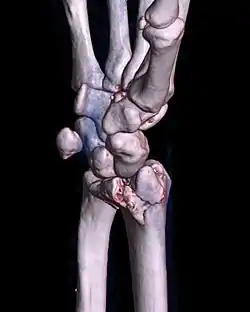

![]() كسر بارتون راحي للمعصم الأيمن، كما يظهر في الاستخلاص ثلاثي الأبعاد لتصوير مقطعي محوسب كسر بارتون راحي للمعصم الأيمن، كما يظهر في الاستخلاص ثلاثي الأبعاد لتصوير مقطعي محوسب | |